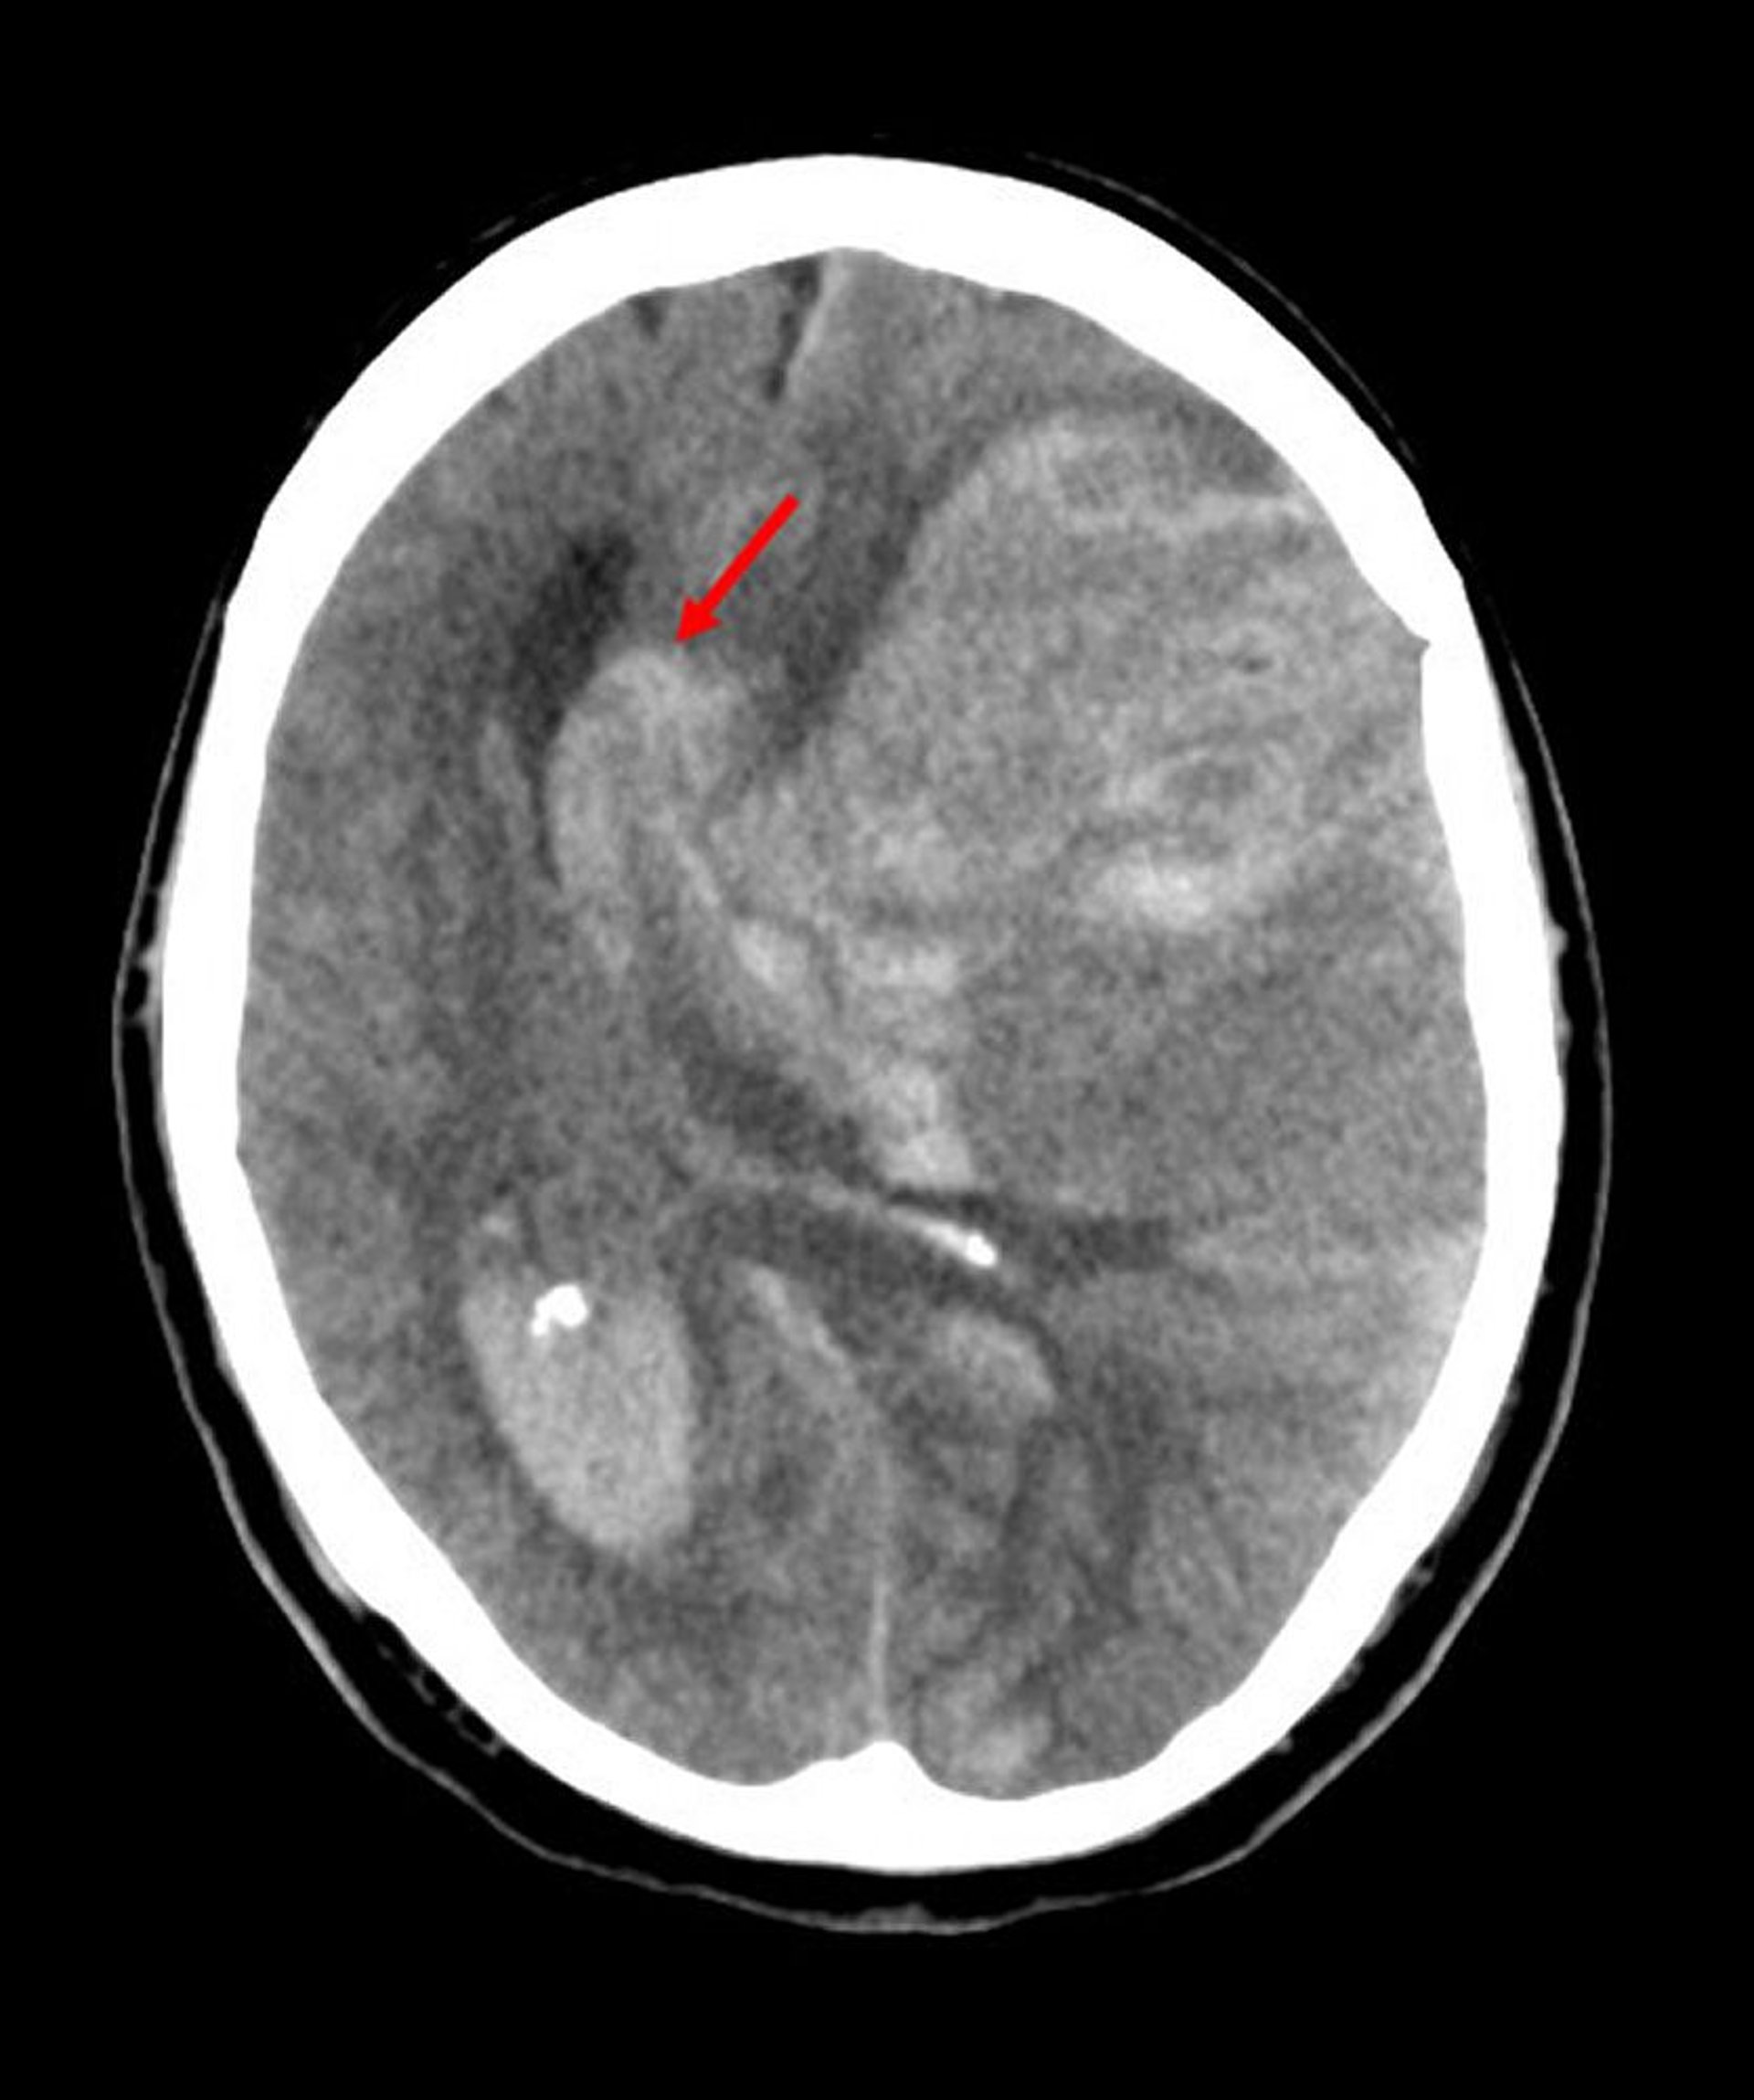

Herniación subfalcina

La herniación subfalcina es el tipo más común de hernia cerebral. En esta imagen, la mitad izquierda del encéfalo se ha herniado por debajo del borde libre de la hoz del cerebro (flecha) porque la hemorragia secundaria a un infarto en la arteria cerebral media aumentó la presión intracerebral.